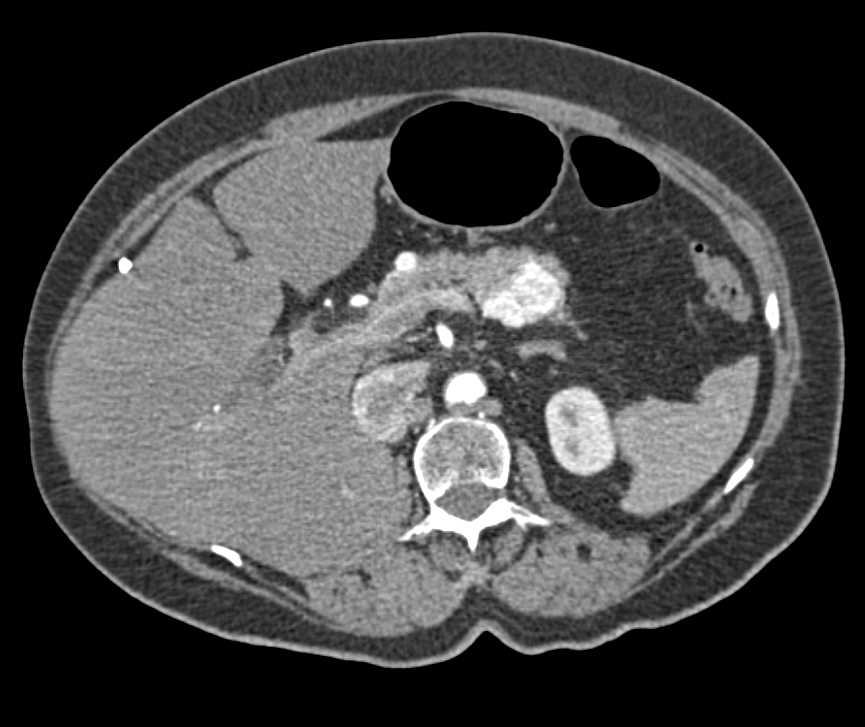

Pancreatic Cancer and Ectopic Pancreas in Duodenum